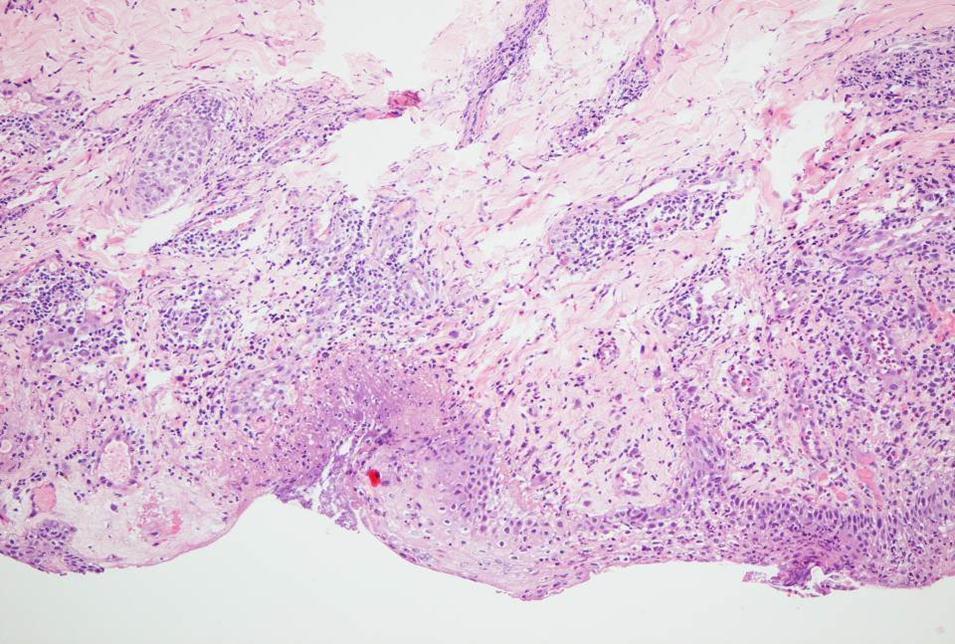

In contrast to IQM alone, the combined use of the fractionated erbium:YAG laser microporation with IQM dominantly induced stronger skin erythema levels starting from visit V2 throughout the last visit V20 (Figure 3a). For the stronger therapeutic responses of crusting and erosions this phenomenon was even more pronounced. By looking at the mean crusting PGA values of V2, V4 and V7 together as early time point of the therapy, arm 2-4 presented with the scores of 0.76±0.3, 1.25±0.2 and 1.3±0.5 compared to the much less pronounced value of crusting in the single IQM control arm-1 with 0.3±0.2. The same is true for the late therapy time point V9/11/13/20 with crusting 2.25±0.8, 2.5±0.5 and 2.3±0.4 arms 2-4 and only 1.3±0.6 in the control arm. For erosions the following mean PGA scores were delineated: V2/4/7 arm 1-4 0.08±0.1, 0.6±0.3, 0.75±0.2, 0.95±0.5 and V9/11/13/20 arm 1-4: 0.5±0.25, 1.2±0.6, 1.37±0.3, 1.44±0.4. Regarding the IQM skin responses no correlation could be found with the amount of shots and pulses used by the laser device. Histopathology of V20 lesional punch biopsies showed in all BCC a dense infiltrate of inflammatory cells which is typical for an adequate IQM response. When this infiltrate was fully replacing signs of BCC the lesions were defined as fully cleared (Figure 4). Within arm 2-4 BCC lesions cleared at 33% (persistent 1 nodular and 1 superficial BCC), 100% and 100% at V20, respectively. Taken together IQM alone led to clearence of 3 out of 4 (75%, persistent a superficial) BCC, though the treatment period was shortened from 6 to 3 weeks. The combined fractionated erbium:YAG laser and IQM application resulted in a slightly better clearance rate of 14 BCC vs. 4 (78%). Notably, those 2 BCC patients, where the laser and IQM application was stopped at V11 also showed full clearence. Figure 5 presents the typical treatment course of a patient in arm 3. Tolerability of the laser microporation was excellent with slight burning or the feeling of small needle sticks during the application. In addition, microporation did not cause any immediate irritation of the skin. Even when erythematous, crusted or eroded IQM lesions were microporated the good tolerability stayed the same. No severe adverse or adverse reactions were noted.

Figure 4.Histopathology of a laser and imiquimod treated basal cell carcinoma at the end of the study (day 20).Focal epidermal necrosis with moderate granulocytic demarcation and reactive perivascular lymphocytic and eosinophilic infiltrates. No residual neoplastic proliferates (HE, x200).